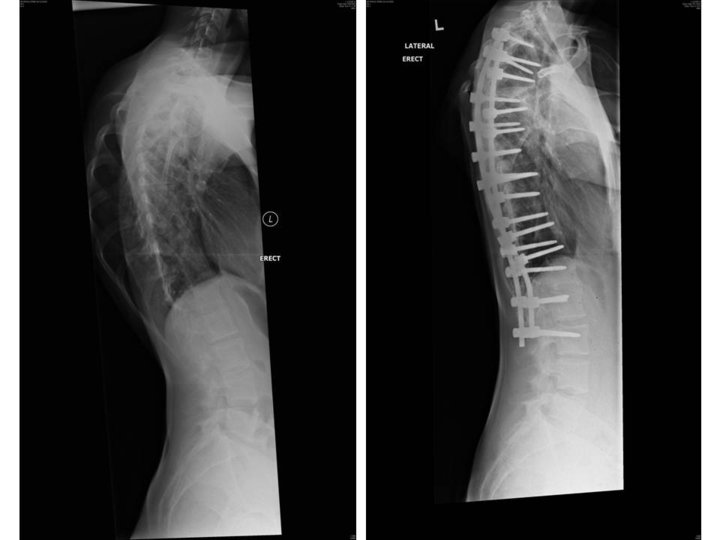

From www.sciencephoto.com

Scoliosis, Before and After Surgery, XRay Stock Image C043/5959 When Can You Shower After Scoliosis Surgery Currently on my 2nd week after my surgery. You might stay the night before or arrive on the morning of your surgery. When you arrive nurses will carry out some tests such as taking your blood pressure and temperature. Your incision will be sealed with a skin “glue”. After your surgery you will be brought to a recovery room and. When Can You Shower After Scoliosis Surgery.

From www.researchgate.net

Xrays after the index surgery showing correction of the scoliosis to When Can You Shower After Scoliosis Surgery Showers should be kept to a minimum, as few as possible. However, you will still need to be careful and try to avoid getting your dressing wet. Cover the bandage with lots of waterproof tegaderms and such. Five (5) to seven (7) days after surgery, you may shower. Your incision will be sealed with a skin “glue”. When can i. When Can You Shower After Scoliosis Surgery.